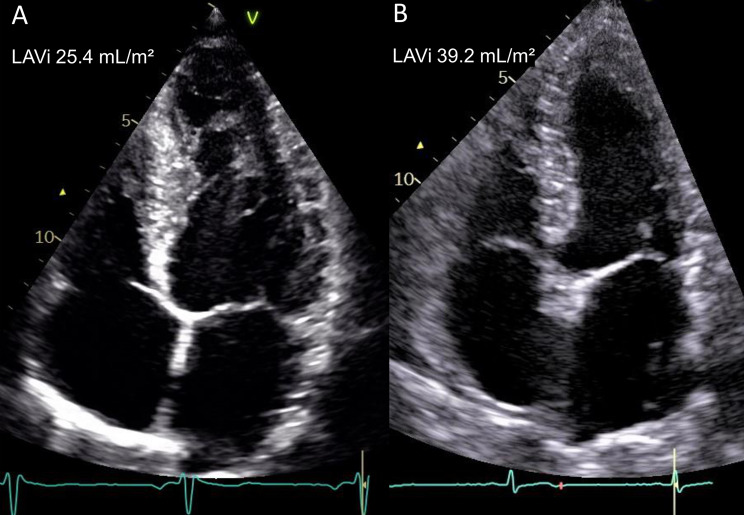

Results: We included 487 patients (69 ± 12 years old, 26% female) with AMI. During the follow-up period all-cause mortality was 50 (10.3%) and patients who reached the primary outcomes were 153 (31.4%). The deceased patients had higher LAVi compared to survivors (40.0 ± 12.9 mL/m2 vs. 29.7 ± 11.2 mL/m2, p < 0.001). Factors associated with all-cause mortality and MACE were age, year of enrollment, left ventricular (LV) ejection fraction, LV global longitudinal strain (GLS), LV filling pressure, moderate or severe mitral regurgitation and LAVi. GLS and EF were segregated into two distinct models due to their moderately high correlation (r = 0.57, p < 0.001). LAVi remained as an independent echocardiographic predictor of primary outcomes after adjusting for the covariates above in two separates multivariable Cox regression models (hazard ratio 1.02/1.02 mL/m2 [95% CI 1.01-1.03/1.01-1.03], p = 0.006/0.003).

Conclusions: Our study demonstrated that LA dilatation is an independent echocardiographic predictor of mortality and MACE in patients with AMI despite improved treatment strategies. This finding highlights the potential of using LAVi as a marker for prognostication in these patients.